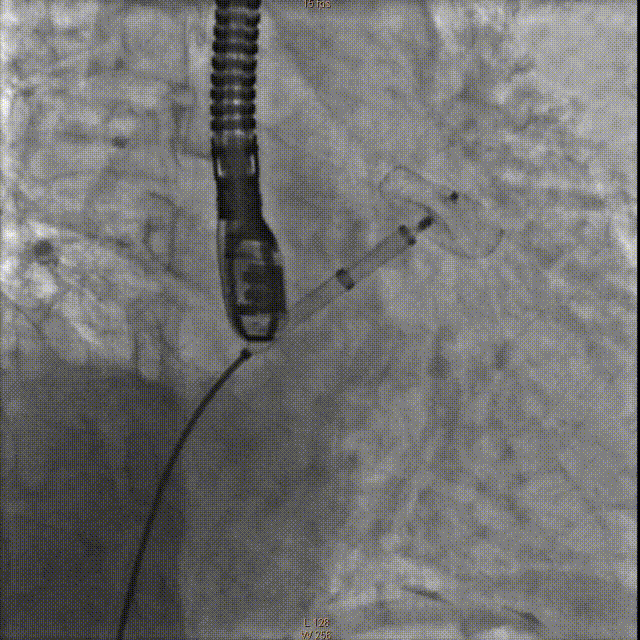

牵拉实验固定稳妥,无明显心包积液,透视下释放左心耳封堵器于左心耳。退出输送鞘管至右房测右房压12/5mmHg:撤出传送钢丝及血管穿刺鞘。

牵拉试验

释放封堵伞